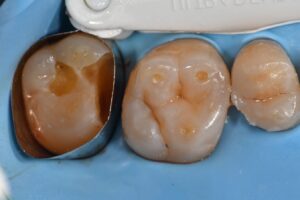

October 13, 2025 Direct Restoration #ClamplessDME #GarrisonCompositight #MajestyES2Universal Previous Post Next Post